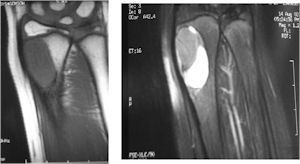

MRI:

- Also useful in determining extent

- There is often extensive edema around the tumor in the surrounding bone and soft tissues that can lead to a misdiagnosis of a malignant tumor.